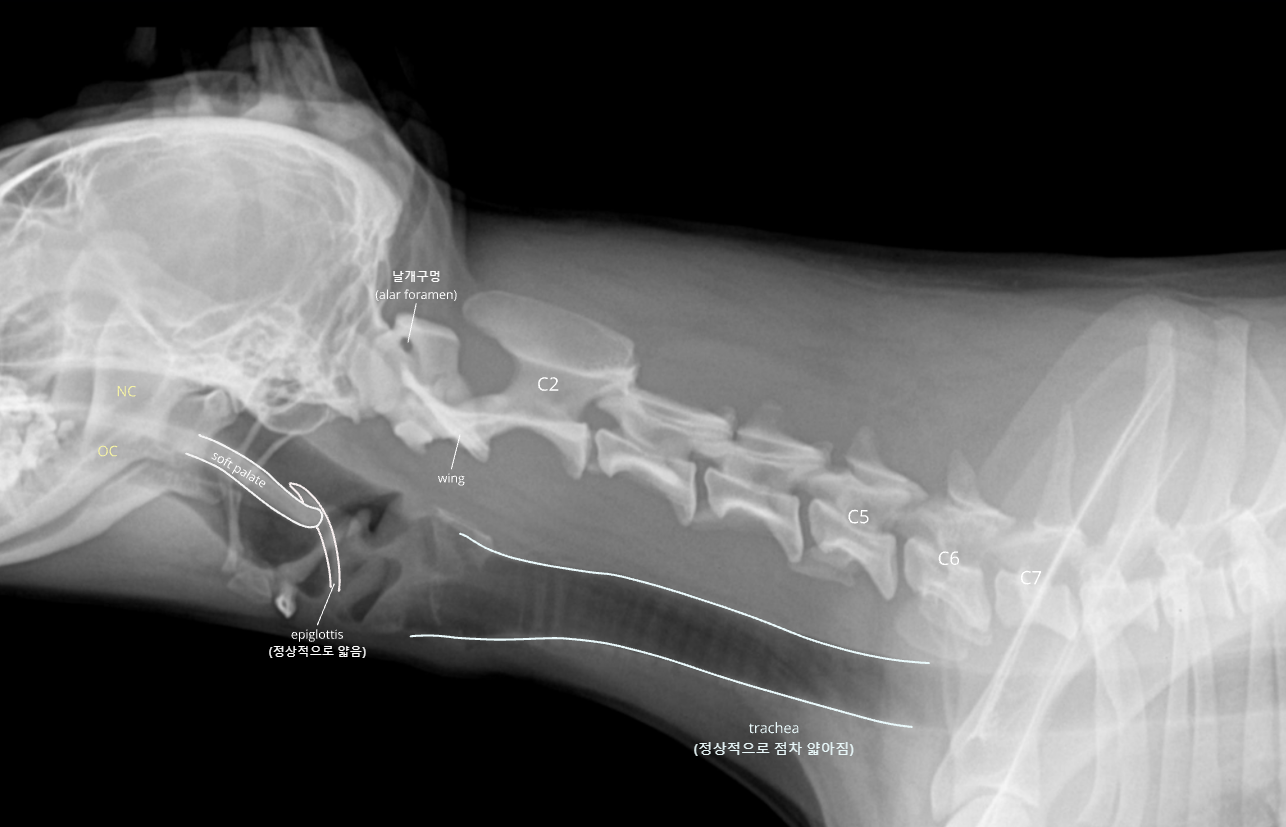

| Upper respiratory system |

![]() |